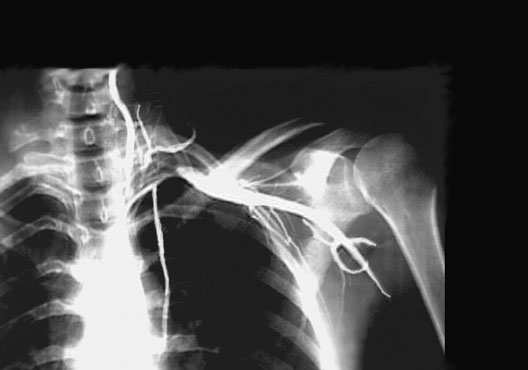

Axilla Angiogram

Roll mouse over image to display labels.

1. Vertebral artery

2. Ascending cervical artery

3. Thyrocervical trunk

4. Transverse cervical artery

5. Axillary artery

6. Circumflex scapular artery

7. Posterior humeral circumflex artery

8. Subscapular artery

9. Brachial artery

10. Internal thoracic artery